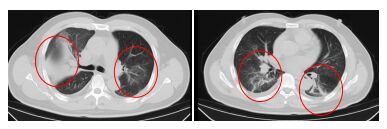

發(fā)熱門診醫(yī)生詳細(xì)詢問顧先生的既往病史,并為其進(jìn)行細(xì)致的體格檢查。胸部CT結(jié)果顯示,顧先生的雙肺存在大面積的炎癥病變。

在感染科醫(yī)護(hù)團(tuán)隊的精心治療與細(xì)致護(hù)理下,顧先生的發(fā)熱、咳嗽、胸悶等癥狀逐漸緩解。復(fù)查的CT結(jié)果顯示,肺部炎癥情況得到了明顯的改善。目前,顧先生已經(jīng)順利康復(fù)出院。